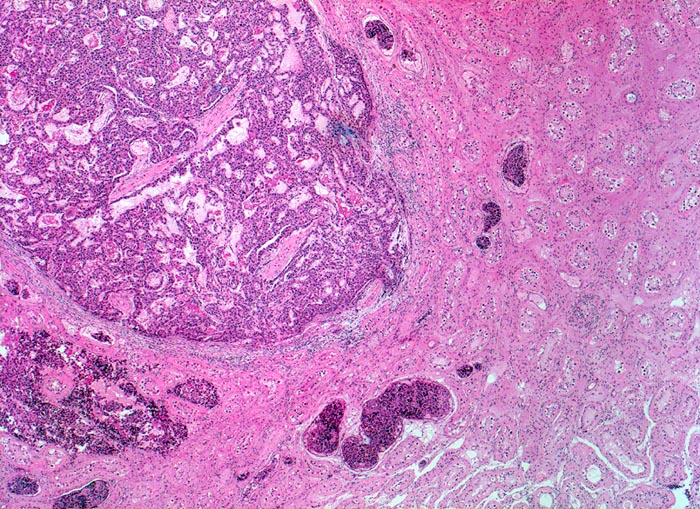

• Polymorphe Tumorzellen bilden miteinander anastomosierende Stränge, solide Zellplatten, glanduläre und kribriforme Strukturen.

• Reichlich ödematöses Stroma mit einzelnen synzytiotrophoblastären Riesenzellen.

• Gefässeinbrüche in peritumoralen Gefässen.

• Tumorinfiltration des peritestikulären Fettgewebes.